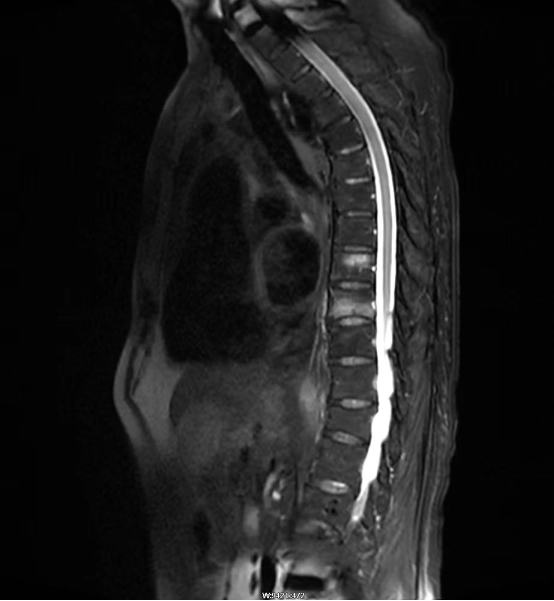

冀某某,男,92岁,4天前因无明显诱因出现腰背部疼痛,起床翻身时疼痛加重,活动受限,遂由家属送来我院就诊。骨二科石华林主任详细查体后,初步考虑患者为“老年性骨质疏松症伴病理性骨折”,结合脊柱核磁共振检查,明确患者胸8、胸9椎体新发骨折。

▲MRI提示胸8、胸9椎体新发骨折